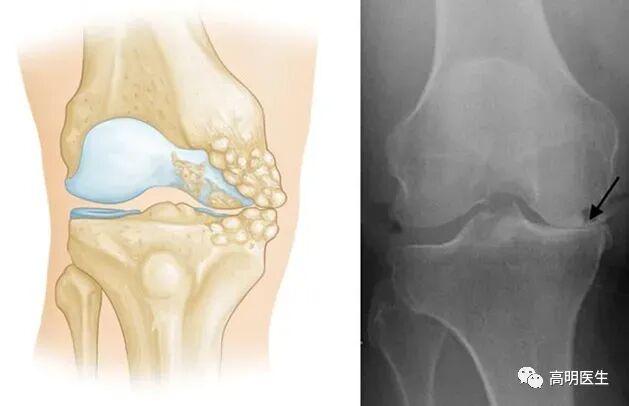

关节炎不是冻出来的

首先明确一点:寒冷刺激不是关节炎的病因。关节炎是一类疾病的统称,包括骨关节炎、类风湿性关节炎、痛风性关节炎等,其中最为常见的是骨性关节炎。膝关节骨性关节炎,是一种膝关节的退行性疾病,主要临床表现为膝关节疼痛、肿胀及活动受限,主要病理表现为膝关节软骨的纤维化、磨损、剥脱等伴发滑膜充血水肿及骨赘增生等。据不完全统计,我国 60 岁以上人群发病率为 50%,75 岁以上人群高达 80%,全国大概有 1.2 亿人遭受膝关节骨性关节炎疼痛的困扰。研究显示膝关节骨性关节炎患者中,近 20%会伴随焦虑及抑郁症状,是导致全世界中老年人生活质量降低和经济负担加重的重要原因。它们的成因各不相同,但都与寒冷无直接因果关系。

· 骨关节炎:最常见的类型,主要由关节软骨的退化引起。年龄增长、肥胖、过度使用关节、遗传因素等才是主要发病原因。

关节就像汽车轮胎,也有“使用寿命”。随着年龄增长,关节软骨逐渐磨损,弹性下降,最终出现骨赘(俗称“骨刺”),这就是骨关节炎的过程 。 只不过有些人的关节耐磨,有些人的不耐磨罢了。不仅人类,几乎所有脊椎动物都会得骨关节炎,但是对于一些关节负荷极小的动物(如蝙蝠、树懒等)发病率极低。这也说明骨关节炎是关节对磨损的自然反应。